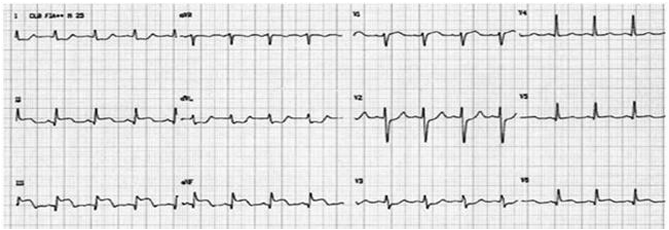

A seguir, está o eletrocardiograma de admissão.

A seguir, está o eletrocardiograma de admissão.